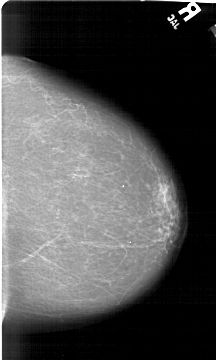

A_1492_1.RIGHT_MLO

RIGHT_CC LINES 6466 PIXELS_PER_LINE 3886 BITS_PER_PIXEL 12 RESOLUTION 43.5 NON_OVERLAY

RIGHT_MLO LINES 6601 PIXELS_PER_LINE 3766 BITS_PER_PIXEL 12 RESOLUTION 43.5 NON_OVERLAY